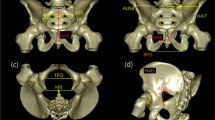

Image data processing was performed on a workstation (OsiriX MD version 11.0.2; Pixmeo SARL, Geneva, Switzerland). Bone kernel was acquired and sent to the workstation. 2D CT images were viewed using a window width and level of 1500 and 300 HU, respectively. Five measurements (Table 1) were performed on left and right proximal femur, respectively. For the measurements of the upper epiphyseal length (UEL), vertical head diameter (VHD), and vertical neck diameter (VND), the coronal oblique plane reconstructed along the middle of the femoral head, neck, and trochanter was used [25] (Fig. 1a). The proximal width (PW) was confirmed in a horizontal section, and the trochanter height (TH) and PW were measured on a plane passing through PW and the superior point of the greater trochanter (Fig. 1b). The measurements were performed manually on CT images to the nearest 0.1 mm.

Two-dimensional computed tomography images showing five femoral measurements (see Table 1 for definition): (a) Upper epiphyseal length (UEL), vertical head diameter (VHD), and vertical neck diameter (VND) on a coronal oblique plane; (b) trochanter height (TH) and proximal width (PW) on a plane passing through PW and the superior point of the greater trochanter